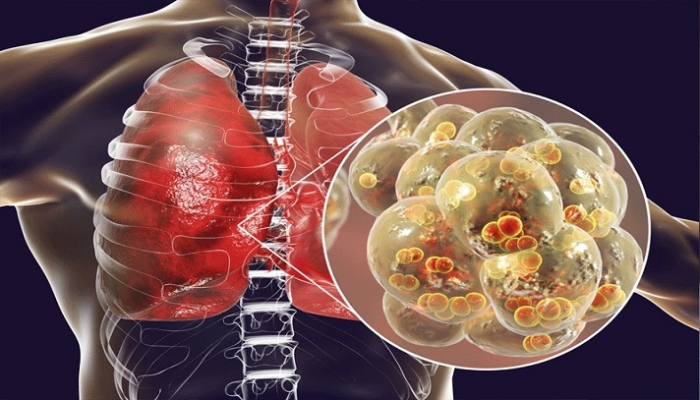

করোনাভাইরাস মোকাবিলায় বিশেষ ন্যানোম্যাটেরিয়াল বানিয়েছে চীন, যা কি না শরীরে ঢুকে মুহূর্তের মধ্যেই ভাইরাসটিকে গিলে খেয়ে ফেলবে। চীনা বিজ্ঞানীরা এমন দাবি করেছেন। ন্যানোম্যাটেরিয়ালটি প্রয়োগ করে ৯৬.৫-৯৯.৯ শতাংশ সাফল্য পাওয়া গেছে বলেও দাবি তাদের।

ভারতীয় সংবাদমাধ্যম নিউজ এইটটিনর খবরেও চীনা গবেষকদের দাবির বিষয়টি তুলে ধরা হয়েছে। সংবাদমাধ্যমটির খবরে বলা হয়েছে, করোনাভাইরাসকে মোকাবিলার জন্য চীনের গবেষকেরা একরকম ন্যানোমেটেরিয়াল বানিয়েছে। শরীরে প্রবেশ করে করোনাভাইরাস শুষে নিয়ে ৯৯.৯ শতাংশ পর্যন্ত নিষ্ক্রিয় করে ফেলে।

বিশেষ এই ন্যানোম্যাটেরিয়ালটিকে ভ্যাকসিন বা ওষুধ বলতে রাজি নন চীনের বৈজ্ঞানিকরা। এটিকে জৈব অস্ত্র বলছেন তারা, যা ভাইরাসটিকে নির্মূল করার জন্য তৈরি করেছেন।

ন্যানোমেটেরিয়াল হেলথকেয়ার ছাড়াও পেন্টস, ফিল্টার, ইনসুলেশন এবং লুব্রিকেট করার কাজেও ব্যবহার করা হয়। গবেষকরা এও দাবি করেছেন, করোনাভাইরাসকে মোকাবিলার ক্ষেত্রে এই ন্যানোম্যাটেরিয়াল দেহে প্রবেশের পর অন্যান্য অ্যানজাইমহগুলোর মতোই কাজ করে।